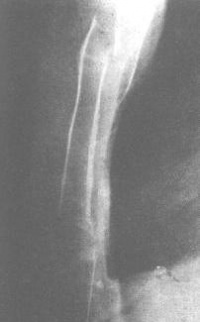

影像学表现]

多为横断形,可有两处以上骨折线,并可发生移位。一般于侧位片显示更佳。